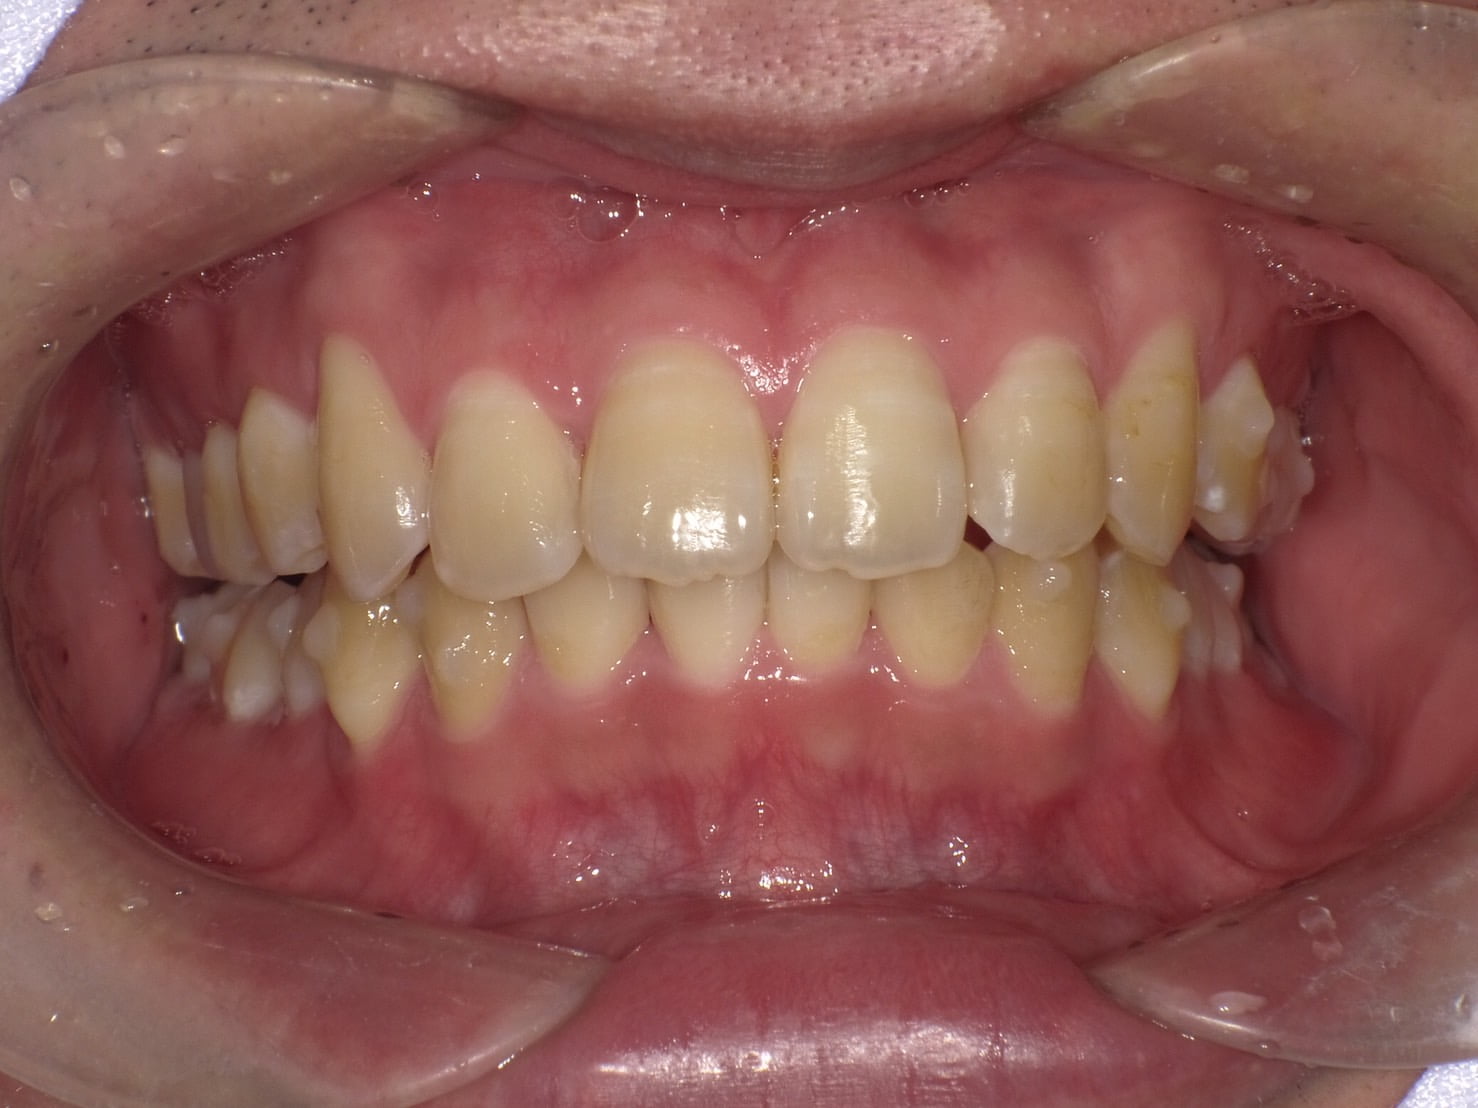

• お悩み

前歯のガタつきが気になる

思いっきり笑えない

年齢

18歳/女性

治療期間

1年8ヶ月

施術説明

歯並びや噛み合わせの不全をアライナー型矯正装置を装着し、歯並びや噛み合わせを改善し適切な状態にする治療です。

副作用

装着したまま糖分の入った飲料を取ると、虫歯を発症しやすくなります。正しい装着方法で1日20時間以上使用しないと、目標とする治療結果を得れないことがあるため、きちんとした自己管理が必要になります。